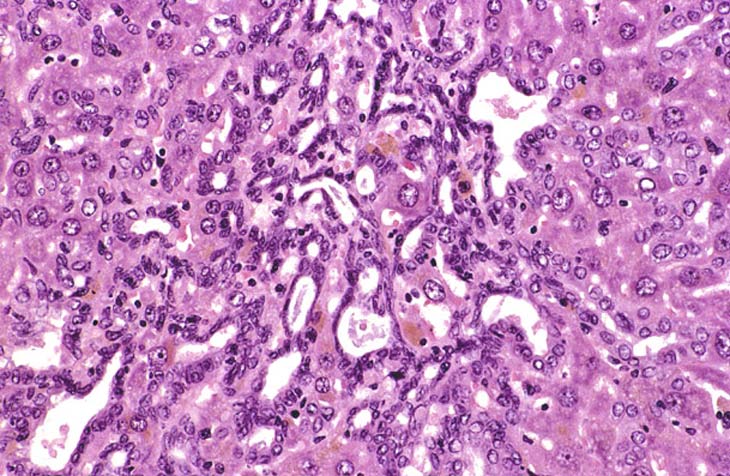

While most examples of bile duct hyperplasia consist of a modest duplication of normal appearing bile ducts in portal areas, occasionally more dramatic examples are found in other areas of the hepatic lobule.

Hyperplastic bile ducts lined by low cuboidal epithelium.